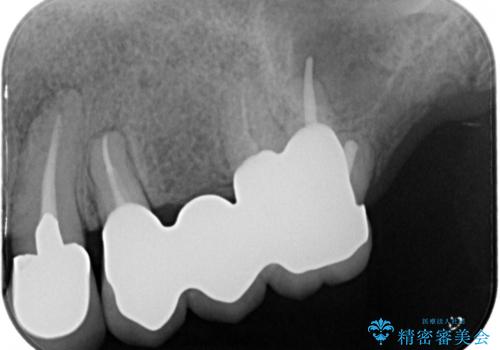

- 奥歯が痛いことを主訴にご来院された患者様です。入院してしまい、治療を2年間放置してしまったとのことでした。

左上は、抜歯とブリッジ治療を行いました(抜歯前に医師と対診)。

左下は、現在も抗がん治療を続けているため、観血的処置(インプラントなどの外科)はなるべく避けたいとのことで入れ歯を希望されました。それに伴い、入れ歯を支える歯のクラウンやりかえも行いました。